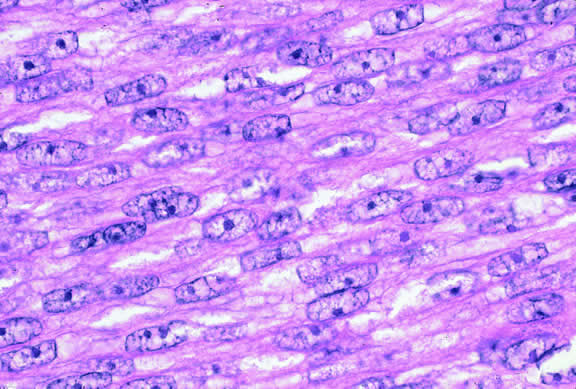

Histopathologically, melanocytomas are composed of cells that have abundant quantities of maximally pigmented cytoplasm that often obscures nuclear details, making microscopic assessment impossible11 (see Fig. 5). Bleached sections, which are a requisite for examination, show that the cells have bland nuclei and a low nuclear-to-cytoplasmic ratio (Fig. 6). Nucleoli usually are inconspicuous, but there are exceptions to the rule. Electron microscopic studies also have revealed a second population of spindle cells.15,24 Melanocytoma cells resemble the benign melanocytes found in the uvea of patients with ocular melanocytosis.

Fig. 6. Melanocytoma, depigmented section. Bleaching of melanin pigment discloses cells with bland nuclei and low nuclear-to-cytoplasmic ratio consistent with benign magnocellular nevus. (Bleach, × 250.)